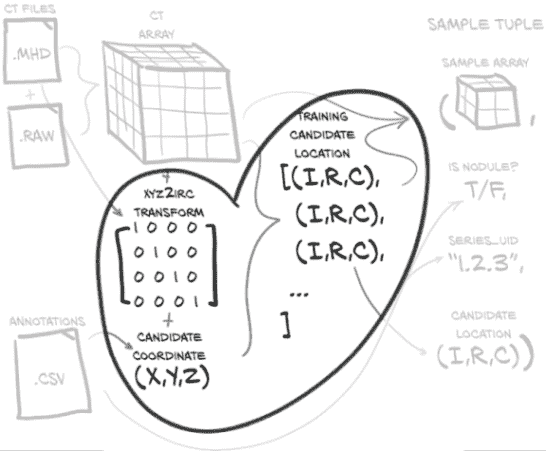

我们的目标是能够根据我们的原始 CT 扫描数据和这些 CT 的注释列表生成一个训练样本。这听起来可能很简单,但在我们加载、处理和提取我们感兴趣的数据之前,需要发生很多事情。图 10.2 展示了我们需要做的工作,将我们的原始数据转换为训练样本。幸运的是,在上一章中,我们已经对我们的数据有了一些理解,但在这方面我们还有更多工作要做。

图 10.2 制作样本元组所需的数据转换。这些样本元组将作为我们模型训练例程的输入。

我们的Ct类将消耗这两个文件并生成 3D 数组,以及转换矩阵,将患者坐标系(我们将在第 10.6 节中更详细地讨论)转换为数组所需的索引、行、列坐标(这些坐标在图中显示为(I,R,C),在代码中用_irc变量后缀表示)。现在不要为所有这些细节担心;只需记住,在我们应用这些坐标到我们的 CT 数据之前,我们需要进行一些坐标系转换。我们将根据需要探讨细节。

我们还将加载 LUNA 提供的注释数据,这将为我们提供一个结节坐标列表,每个坐标都有一个恶性标志,以及相关 CT 扫描的系列 UID。通过将结节坐标与坐标系转换信息结合起来,我们得到了我们结节中心的体素的索引、行和列。

使用(I,R,C)坐标,我们可以裁剪我们的 CT 数据的一个小的 3D 切片作为我们模型的输入。除了这个 3D 样本数组,我们必须构建我们的训练样本元组的其余部分,其中将包括样本数组、结节状态标志、系列 UID 以及该样本在结节候选 CT 列表中的索引。这个样本元组正是 PyTorch 从我们的Dataset子类中期望的,并代表了我们从原始原始数据到 PyTorch 张量的标准结构的桥梁的最后部分。